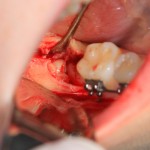

Итак, на фото вы видите шестерку и наклеенные брекеты. Последние несколько осложняют нашу работу, существует риск, что мы случайно один из брекетов оторвем — и об этом мы предупреждаем нашу пациентку.

Далее, разрез. Создаем доступ к зубу. Для этого используется повышающий наконечник с соответствующими фрезами. Вот они, восьмерка и семерка: